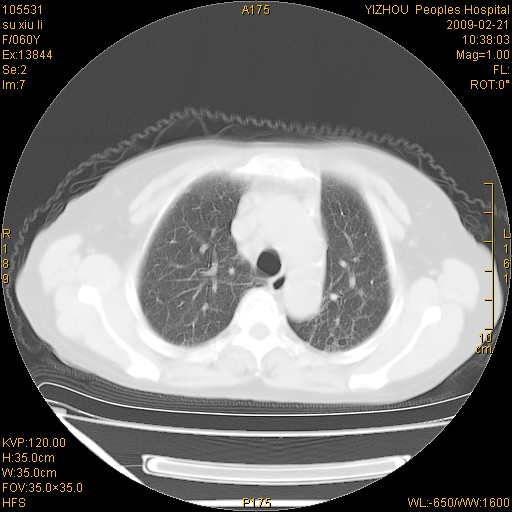

标题: CT18259:两肺间质纤维化? [打印本页]

标题: CT18259:两肺间质纤维化?

女,60岁,反复咳嗽1月。

两肺支扩,以肺为著合并双肺较广范纤维化病变。建议除外结核等病变。

间质性肺炎

符合间质感染,部分纤维化表现

特发性间质纤维化

特发性间质纤维化伴支扩!